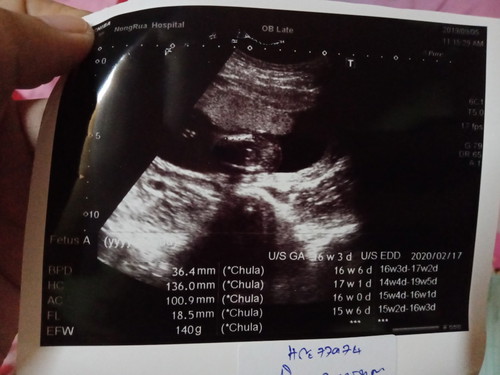

ท้อง17สัปดาห์ ได้ไปอันเตอร์ซาว2รอบแล้ว ดูให้หน่อยค่ะ ว่าเป็นผู้หญิงหรือผู้ชายค่ะ หมอยังไม่บอกเพศเรยค่ะ